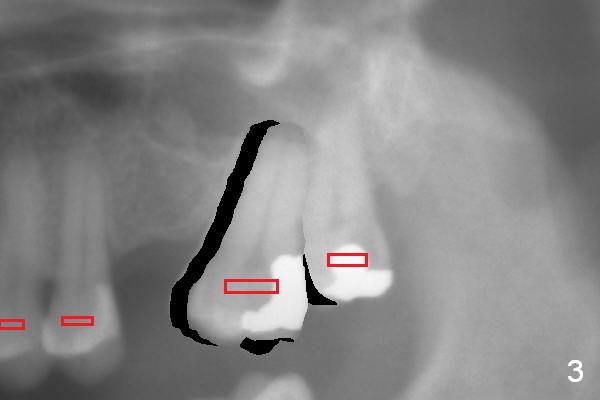

A second option for #14 is segmental orthodontic treatment. Initially keep the tooth #16 and mesial reduction (Fig.2 *). Place brackets between #11 and 16 (Fig.3 red) and open coil spring between #13 and 15.